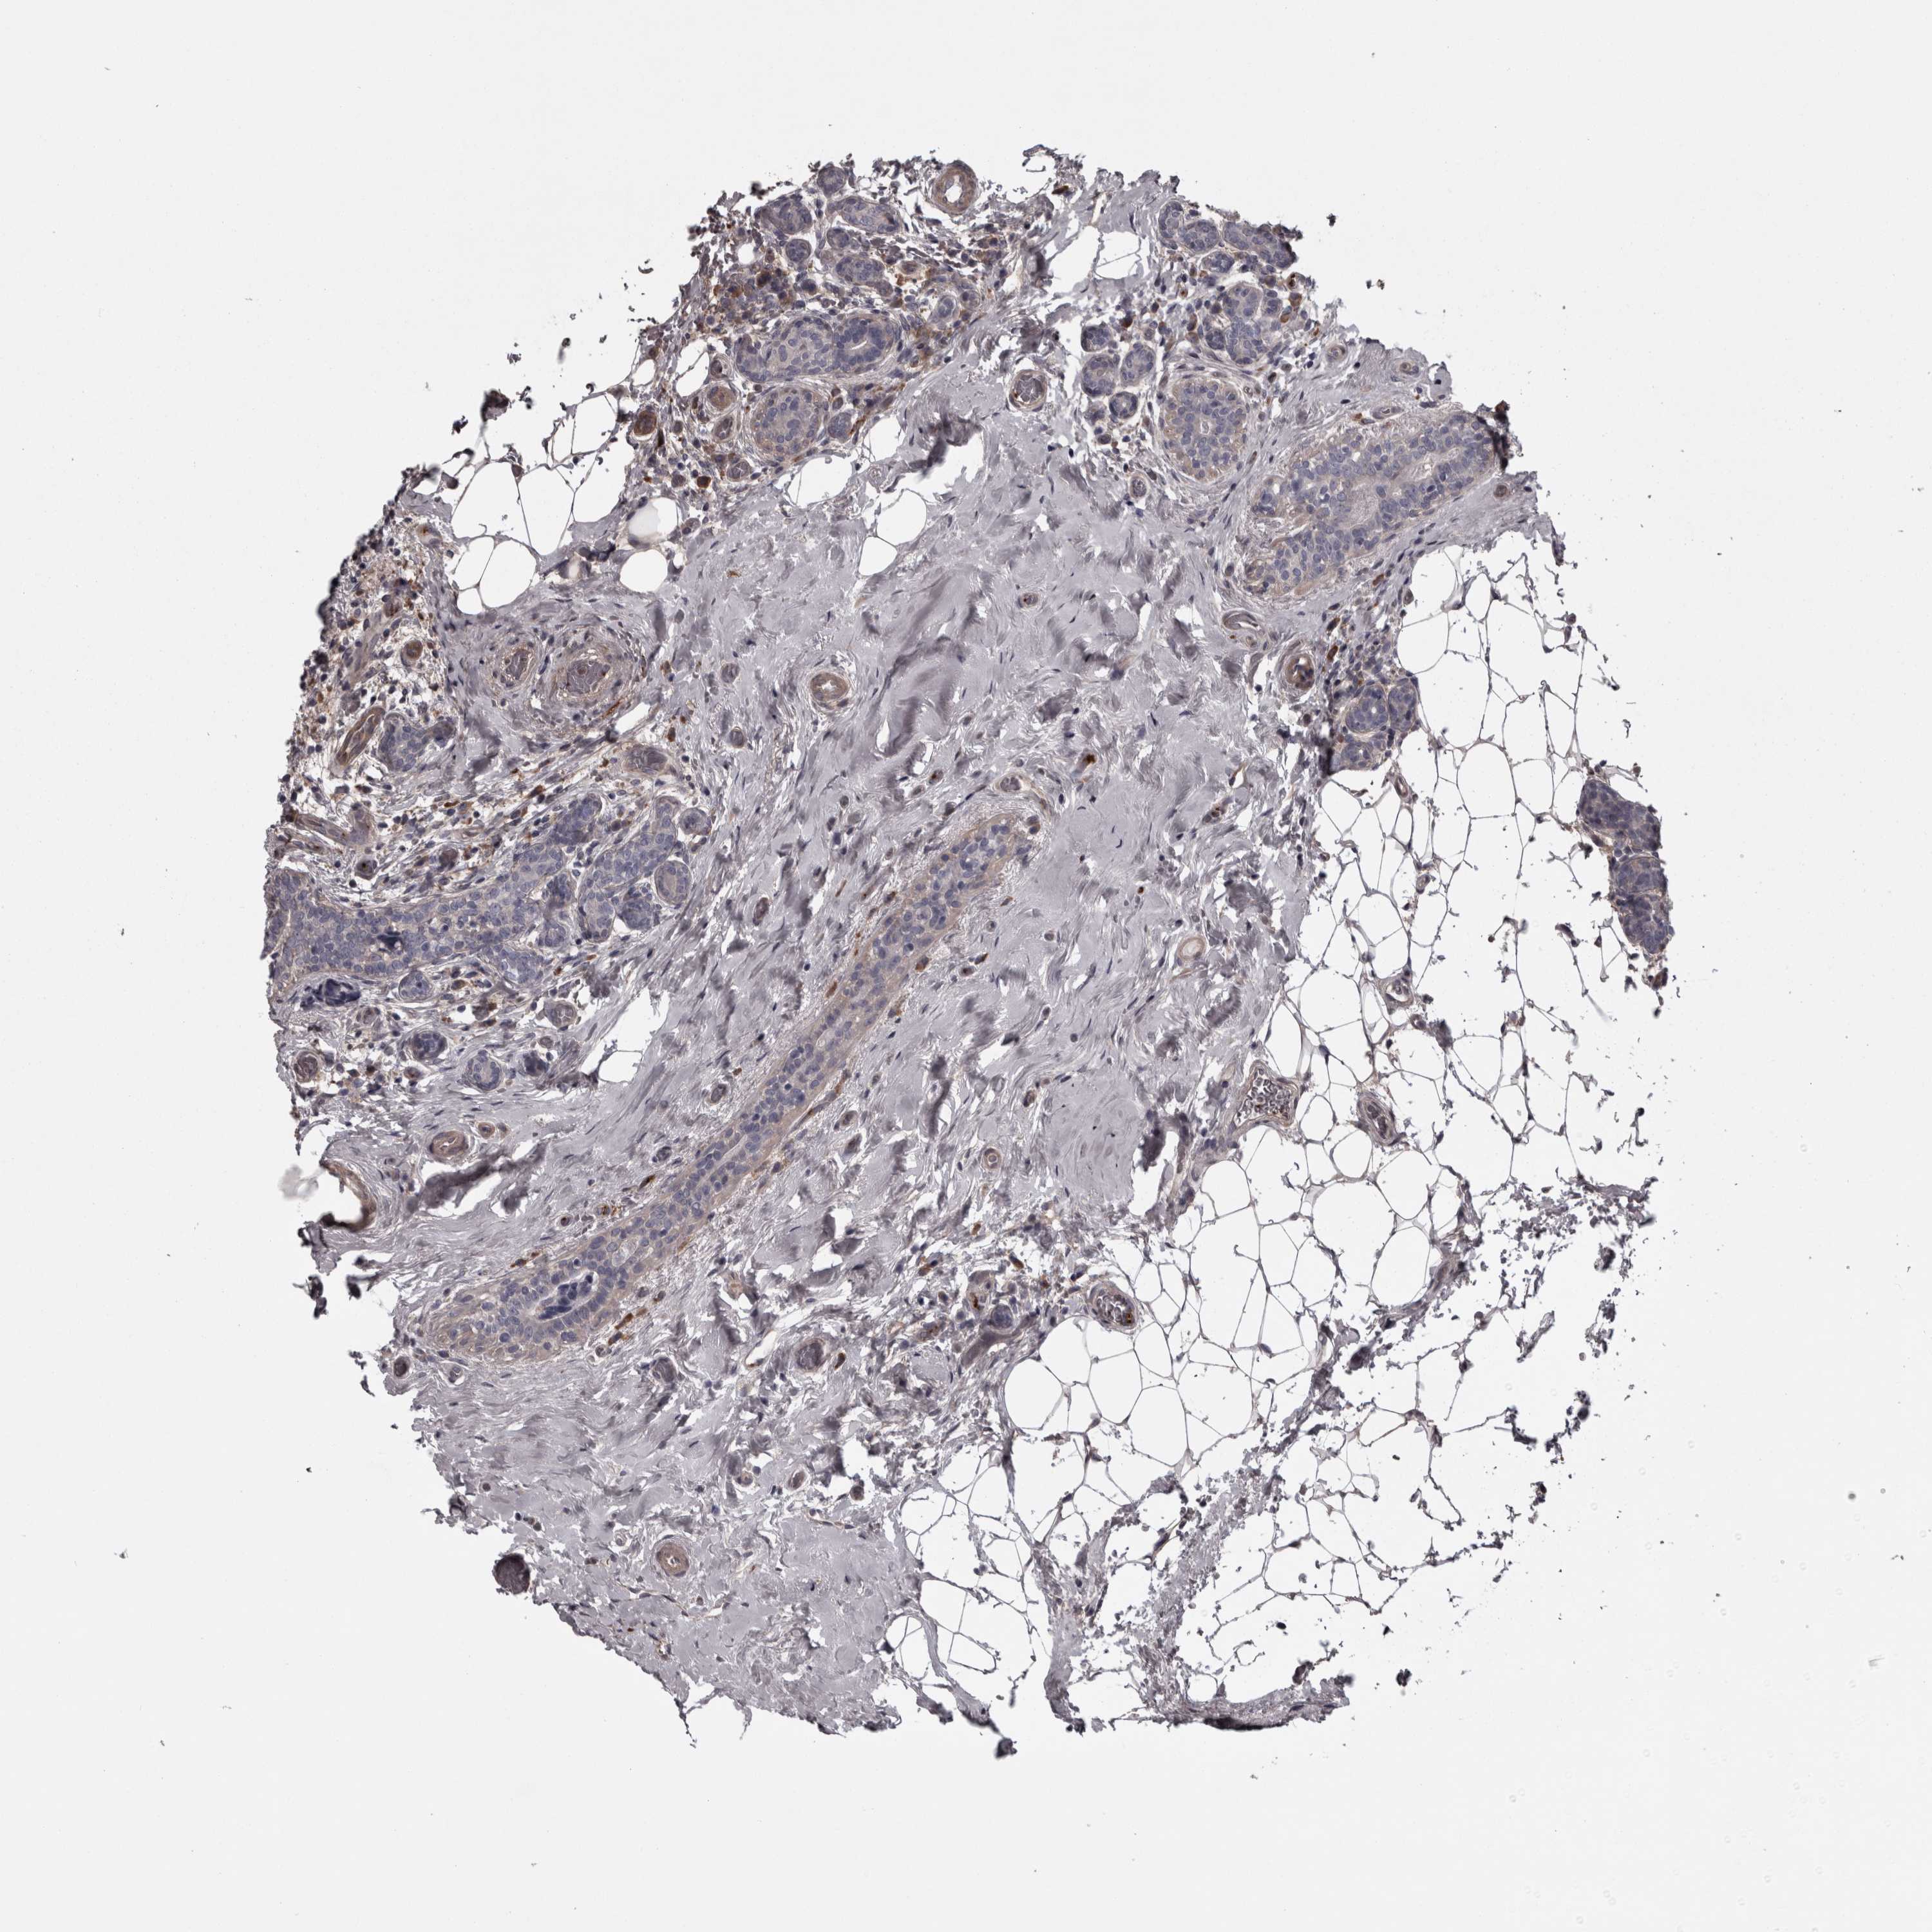

CANCER BREAST CANCER Show tissue menu

BRCA TCGA BRCA VALIDATION PROTEIN EXPRESSION